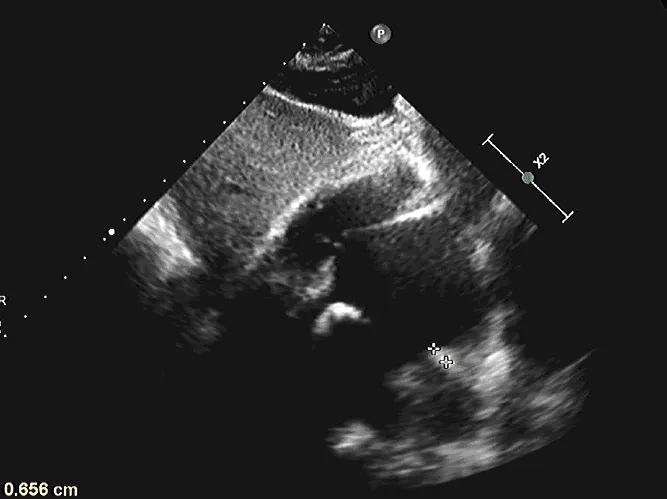

释放后超声

释放封堵器后,封堵器盘面稳固贴壁,成型良好,超声下未见分流,封堵成功。

四腔心切面下观察封堵器,左右盘面稳固贴壁,盘面平整,未影响瓣膜结构

主动脉短轴切面下观察封堵器,封堵器形态稳定,无残余分流